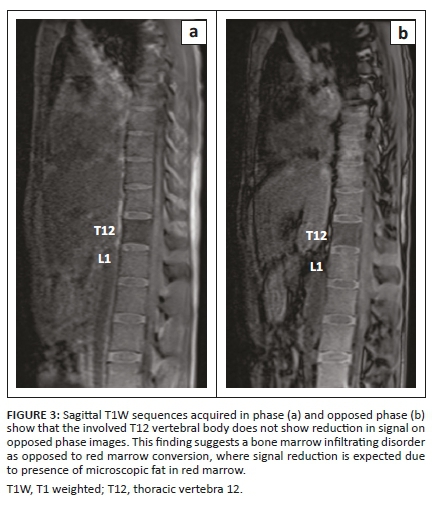

The MRI examination revealed altered signal intensity involving the bodies and posterior elements of the T12 vertebra and L1 vertebra which showed hypointense signal on T1 weighted (T1W) and hyperintense signal on T2W and short tau inversion recovery (STIR) sequences (Figures 1 and 2) with mild enhancement on post contrast images. On chemical shift imaging, the involved vertebral body did not show reduction in signal on opposed phase images (Figure 3). There was a homogeneously enhancing soft tissue mass in the posterior epidural space extending from the T12 to L2 vertebral levels appearing isointense on T1W and hyperintense on T2W and STIR images (Figures 2 and 4). The lesion caused narrowing of the spinal canal with marked compression of the conus medullaris and cauda equina nerve roots. There was associated widening of bilateral neural foramina (right > left) at the T12-L1 and L1-L2 levels, with infiltration of the soft tissue lesion into bilateral paraspinal muscles. A possibility of myeloid sarcoma was suggested given the clinical profile and imaging findings.

A precise and prompt diagnosis of chloroma is crucial as it allows the institution of definitive radiotherapy or adjuvant chemotherapy for local control of the disease, which helps in relieving cord compression and obviates any unnecessary surgery. Magnetic resonance imaging forms the cornerstone in the evaluation and diagnosis of spinal involvement in chloroma by aiding in spatial localisation (i.e. vertebral, epidural, intradural extramedullary and intramedullary), determining its extent and assessing the degree of cord compression, if present. At MRI, vertebral involvement in chloroma manifests as focal, multifocal or diffuse leukaemic infiltration of the vertebral marrow with low signal intensity on T1W, high signal intensity on T2W images and avid enhancement on post contrast images. Chemical shift imaging remains a useful entity when differentiating this condition from red marrow conversion. A propensity for ligamentous and subperiosteal involvement is also seen as a result of spread via the haversian canals.6 However, this non-specific appearance can be confused with marrow infiltrating disorders such as multiple myeloma and lymphoma; hence, a thorough clinical history of haematological disease is imperative in establishing the diagnosis.